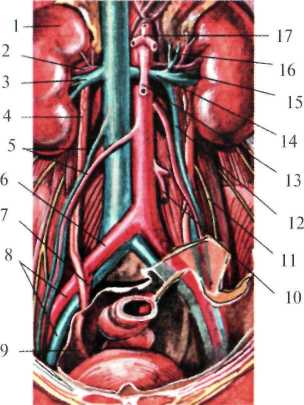

Кнутри от правого мочеточника лежит нижняя полая вена. В верхней части правый мочеточник прикрыт нисходящей частью 12-перстной кишки, ниже – корнем брыжейки тонкой кишки. Кнаружи от мочеточника лежит восходящая ободочная и слепая кишка. Червеобразный отросток через листок париетальной брюшины может тесно соприкасаться с подвздошным отделом мочеточника, что необходимо иметь в виду, т.к. при камнях мочеточника, расположенных в данном отделе, болевой симптом может быть принят за острый аппендицит. Кнутри от левого мочеточника лежит аорта, кнаружи – нисходящая ободочная кишка, спереди – париетальная брюшина и корень брыжейки сигмовидной кишки (рис.2.7).

| Рис. 2.7. Мочеточники в забрюшинном пространстве (по Неттеру, с изменениями). 1 – ren dexter, 2 – a. renalis dexstra; 3 – v. renalis dexstra; 4 – ureter dexter; 5 – a., v. testicularis; 6 – a. iliaca communis; 7 – a. iliaca interna; 8 – a., v. iliaca externa; 9 – контур мочеточника под брюшиной (тазовый отдел); 10 – a. mesenterica inferior; 11 – п. genitofemoralis; 12 – v. testicularis sinistra; 13 – a. mesenterica superior; 14 – v. renalis sinistra; 15 – v. suprarenalis; 16 – a. suprarenalis; 17 – truncus coeliacus. |